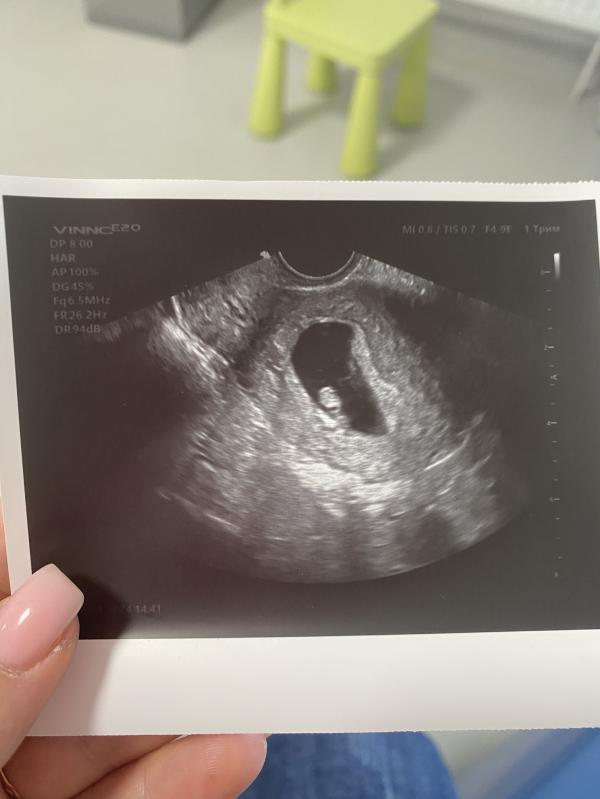

Сладкое сердечко - слушаем?

Все хорошо🩷

Слушали сладкое сердечко